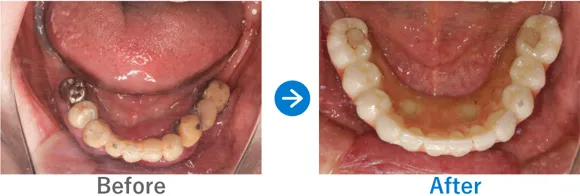

Case3

重度の歯周病を罹患された方。フルマウスインプラント治療直後に仮歯が入り感動されたケース

全顎上下共にブリッジ治療されている。重度の歯周病で歯がグラグラしている。

上下、ALLON4

5,884,000円(上下総額/内訳:上顎オールオン4(ノーベルインプラント4本)、下顎オールオン4(ノーベルインプラント4本)、3Dモデルガイド*、仮歯、セデーション、ボツリヌストキシン注射、3D模型、保証10年)

来院の背景

全体的に重度の歯周病に罹患しており、歯がグラグラしており抜けそうで咬めない、食事ができなく困っていた。インプラントを検討していたが他院で800万円〜900万円と聞いた。デンタルローンを申請。

治療結果

上下のALLON4を実施して治療同日に上下手術を行った。治療後すぐに仮歯が入ったので、とても喜んでいただいた。治療終了。メンテナンス来院継続中。

現在、セルフケアもしっかりされていて、メンテナンスも欠かさず来院していただいているため、インプラントは問題なく使えています。先日、横浜院で10年ぶりくらいにお会いしたのでご挨拶したら、とても喜んでくださりました。あの時インプラントの決断をして良かったと仰っていました。